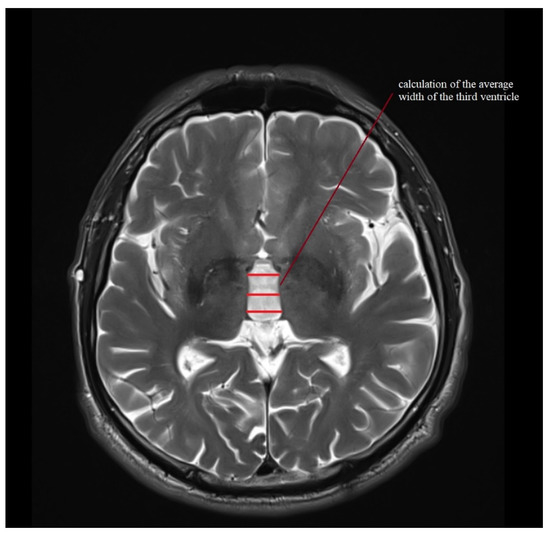

| III ventricle (mm) | 7.6 (4.2–12.5) | 2.2 ± 1.6–3.4 | 11.1 (6–16) | 2.5 ± 1.8–4 | 12.2 (5–19) | 3.1 ± 2.4–4.6 | 9.4 (6–14) | 2.5 ± 1.9–3.6 | 10.3 (7–14) | 2.1 ± 1.6–3.1 |

| III Ventricle | PONS (cm2) | MIDBRAIN (cm2) | M/P Ratio | MRPI | MRPI 2.0 | |

| control | 0.9215 | 1.0 | 0.0002 | 0.0001 | 0.0052 * | 0.0006 |

| PSP-RS | 1.0 | 1.0 | 1.0 | 1.0 | 1.0 | 1.0 |

| MSA-P | 0.9115 | 1.0 | 0.0016 | 0.0008 | 0.0003 | 0.0038 * |

| CBS | 1.0 | 1.0 | 1.0 | 1.0 | 1.0 | 1.0 |